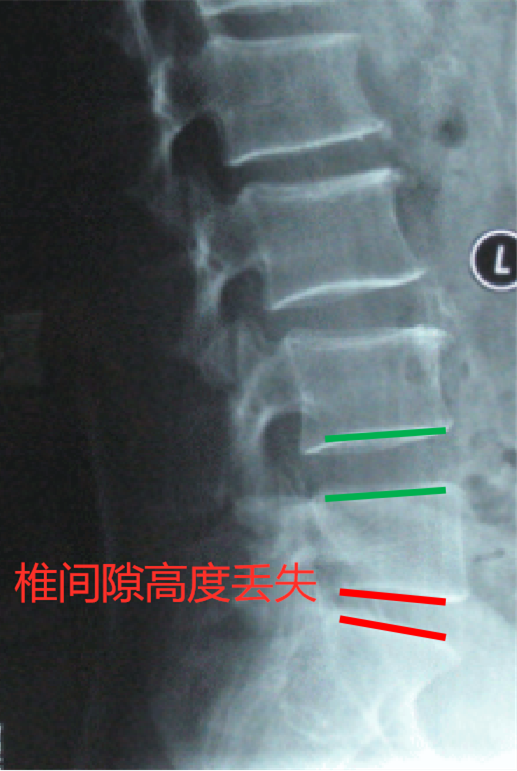

1、腰椎 X 线

X 线片虽不能提供腰椎间盘突出症的直接证据,但是可以帮助鉴别诊断,也可根据椎间隙高度的丢失获得一些间接诊断。

图源:作者提供